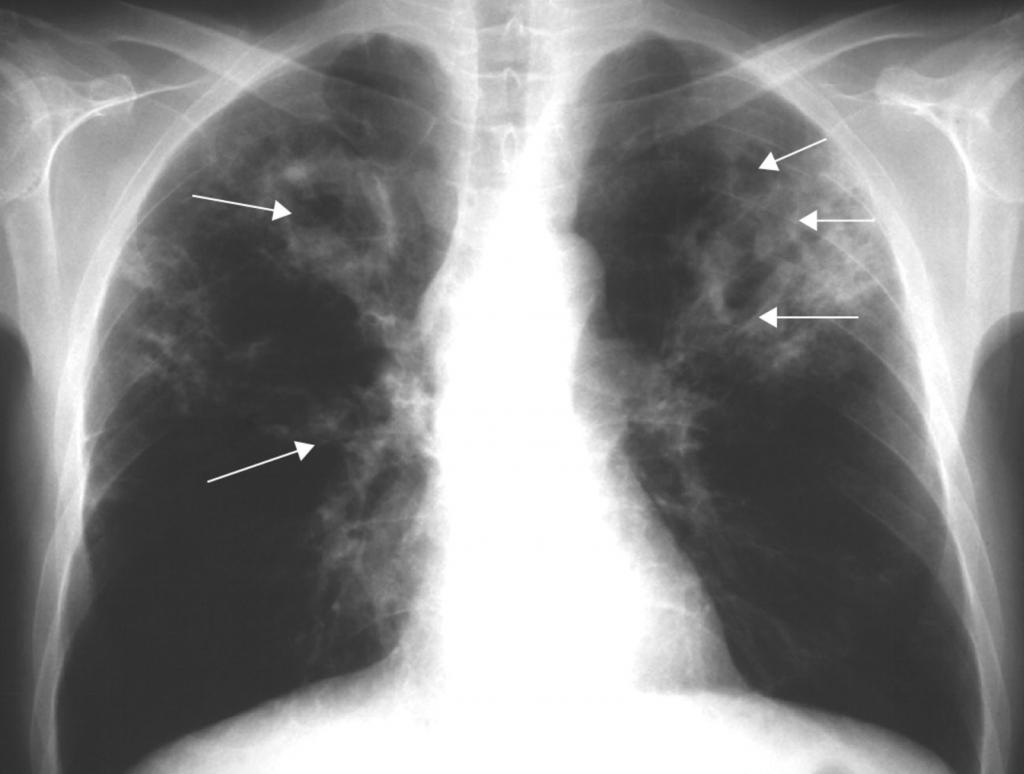

То, как выглядит туберкулез на снимке, зависит как от характера его распространения, так и от остроты процесса. Наиболее характерный подтип диссеминированного туберкулеза — милиарный туберкулез. Он представляет собой острую, чаще всего гематогенную инфекцию.

Ниже перечислены основные его признаки на рентгене:

• большое количество мелких очагов, несколько миллиметров в диаметре;

• очаги равномерно распространены по всему легочному полю;

• иногда очаги сливаются;

• корни легких несколько приподняты;

• иногда объем легочной ткани становится меньше.